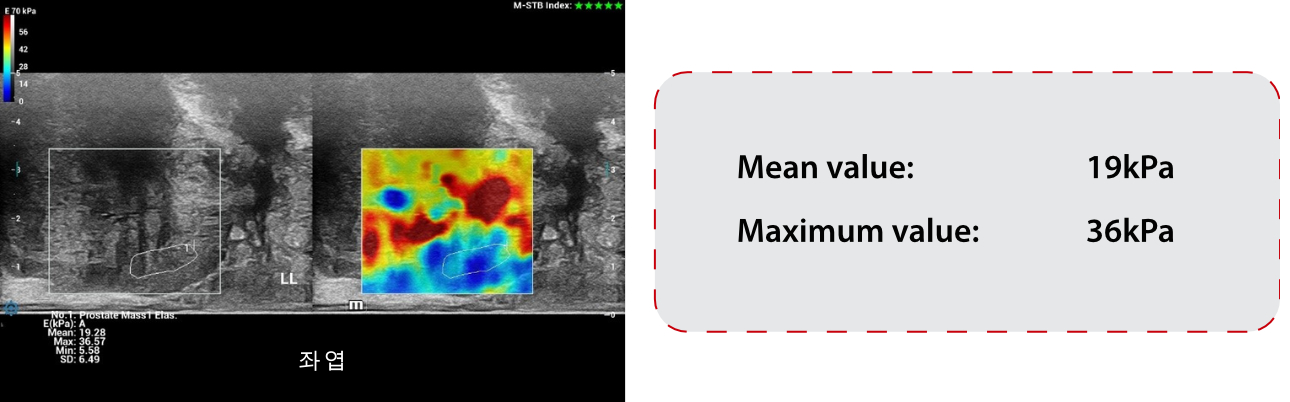

??? ?? ???(SWE) ??:

STESWE ŌĆō ??? ?? ???:

??? ?? ???(SWE)? ??? 34kPa, ??? 115kPa? ?? ??(??6). ?? ??? SWE? ???? ? ???? ? ??.(?? = 19 kPa, ?? = 36 kPa). (??7) ????? ??? ????(PZ)?? ???? ?? ???? ???. ????(TZ)? ??? ???? ?? ????(PZ)?? ? ???. ????(TZ)? ????(PZ)? ??? ???.

- ?? STE? ??? ?? ?? ???? ??????, ?? ???? 19kPa, ?? 36kPa????.